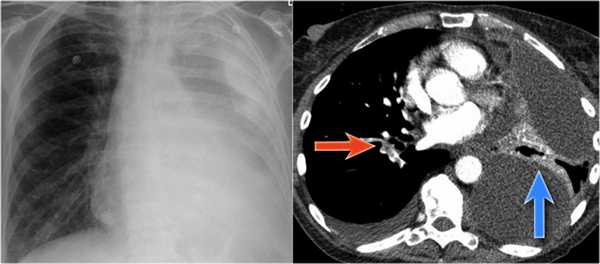

На нижепредставленой рентгенограмме пациента 70 лет, упавшего с лестницы, в плевральной полости определяется скопление жидкости, предположительно являющейся кровью.

Это ателектаз нижней доли правого легкого.

Обратите внимание на правую границу сердца. Правая междолевая артерия не видна потому, как она не окружена воздушной легочной тканью, а закрыта спавшейся нижней долей правого легкого.

Ниже представлены последующие рентгенограммы органов грудной полости того же пациента, на которых ателектаз разрешен.

Обратите внимание на правую междолевую артерию (красная стрелка) и границы правых отделов сердца (синяя стрелка).